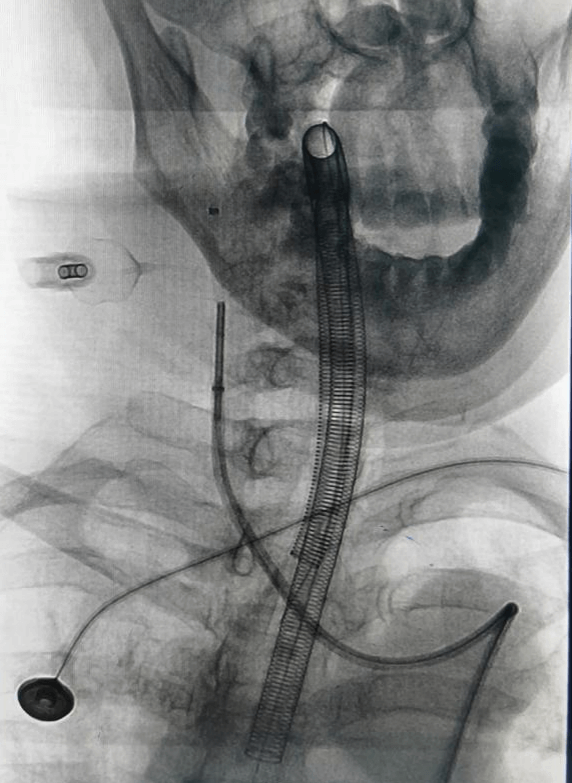

神经外科介入团队在张德辉院长的带领下,迅速启动救治方案,与患者家属充分沟通交流病情,告知患者血管条件差,手术中,医生们面临着巨大挑战,患者血管呈II型弓且迂曲严重,手术难度极高,导管到位困难,若双侧动脉瘤同时处理,手术风险极高,尽量争取一次手术解决双侧动脉瘤。

手术中造影可见右侧动脉瘤破裂小泡,为责任动脉瘤,术中予以支架辅助栓塞,考虑患者血管条件极差,若左侧同期处理,手术时间较长,容易形成血栓,增加手术风险,团队决定先处理责任动脉瘤,左侧后交通动脉瘤择期处理。